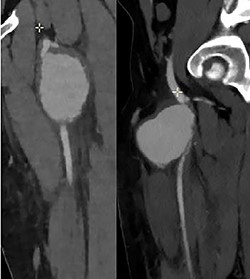

Ultrasonography (US) of the left thigh showed an aneurysmal dilatation of the SFA measuring 67 × 50 × 80 mm (Fig. 2) on the anterior aspect of the proximal third of the thigh. Computer tomography angiogram (CTA) confirmed a 64 × 80 × 87-mm PSA developed on the anterior side of the proximal left SFA (Fig. 3). The other arterial axes were healthy and normal. Supplementary imaging examinations did not identify any additional aneurysms.

Computer tomography angiogram showed a PSA of the proximal SFA.

The CTA confirmed a PSA measuring 13 mm in diameter (Fig. 6B).

Unfortunately, in the meantime, he presented to the emergency room for a swelling of his left thigh since the morning. He had no pain. He was hemodynamically stable. His hemoglobin was 13 g/dl. We examined a large pulsatile mass of the left upper leg. The CTA showed a PSA (8.3 × 10.7 × 9 cm) of his left SFA and a hematoma with active bleeding on the anterior aspect of the left thigh, in close contact with the left SFA (Fig. 7).